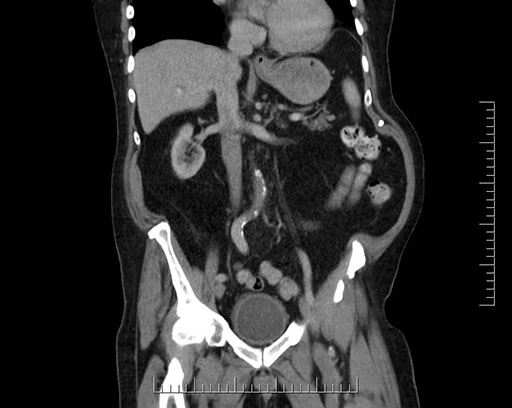

Imaging Analysis

Look through the patient's CT scan to identify any areas of concern for the necessary procedure.

Based on your CT findings, which issue(s) would give reason for "planned slowing down moment(s)" in this case?

Considering a standard Whipple procedure, what step(s) of the operation would you do differently in this case?